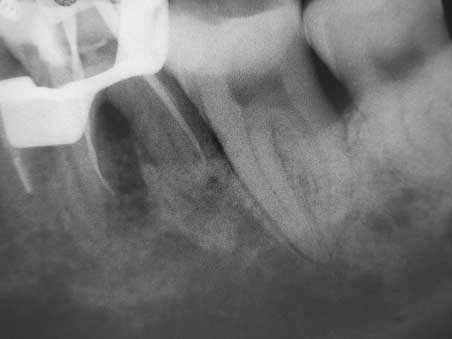

Veröffentlicht 30. November 2008 am 452 × 339 in 3 mesiale Kanalausgänge (1)

Meßaufnahme